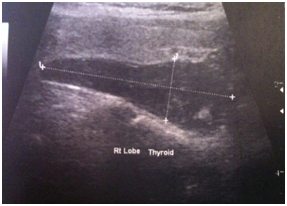

Biology: PTH>560pg/mL (dosed twice) with a calcemia>130mg/L, creatinine clearance=24mL/min. This chronic renal failure has long been considered secondary to a diabetic nephropathy but the chronic renal failure was strongly in favor of an interstitial nephropathy secondary to a chronic hypercalcemia because there was not any diabetic retinopathy. The cervical ultrasound showed a macro parathyroid nodule (45mm, (Figure 1). The osteodensitometry revealed an osteoporosis (T Score<-2.5). The patient received an adequate hydration and bisphosphonate treatment (three injections of ibandronic acid) before addressing her for the parathyroid surgery.

Figure 1 Cervical ultrasound: oval, hypoechoic, right parathyroid nodule (45/14mm).